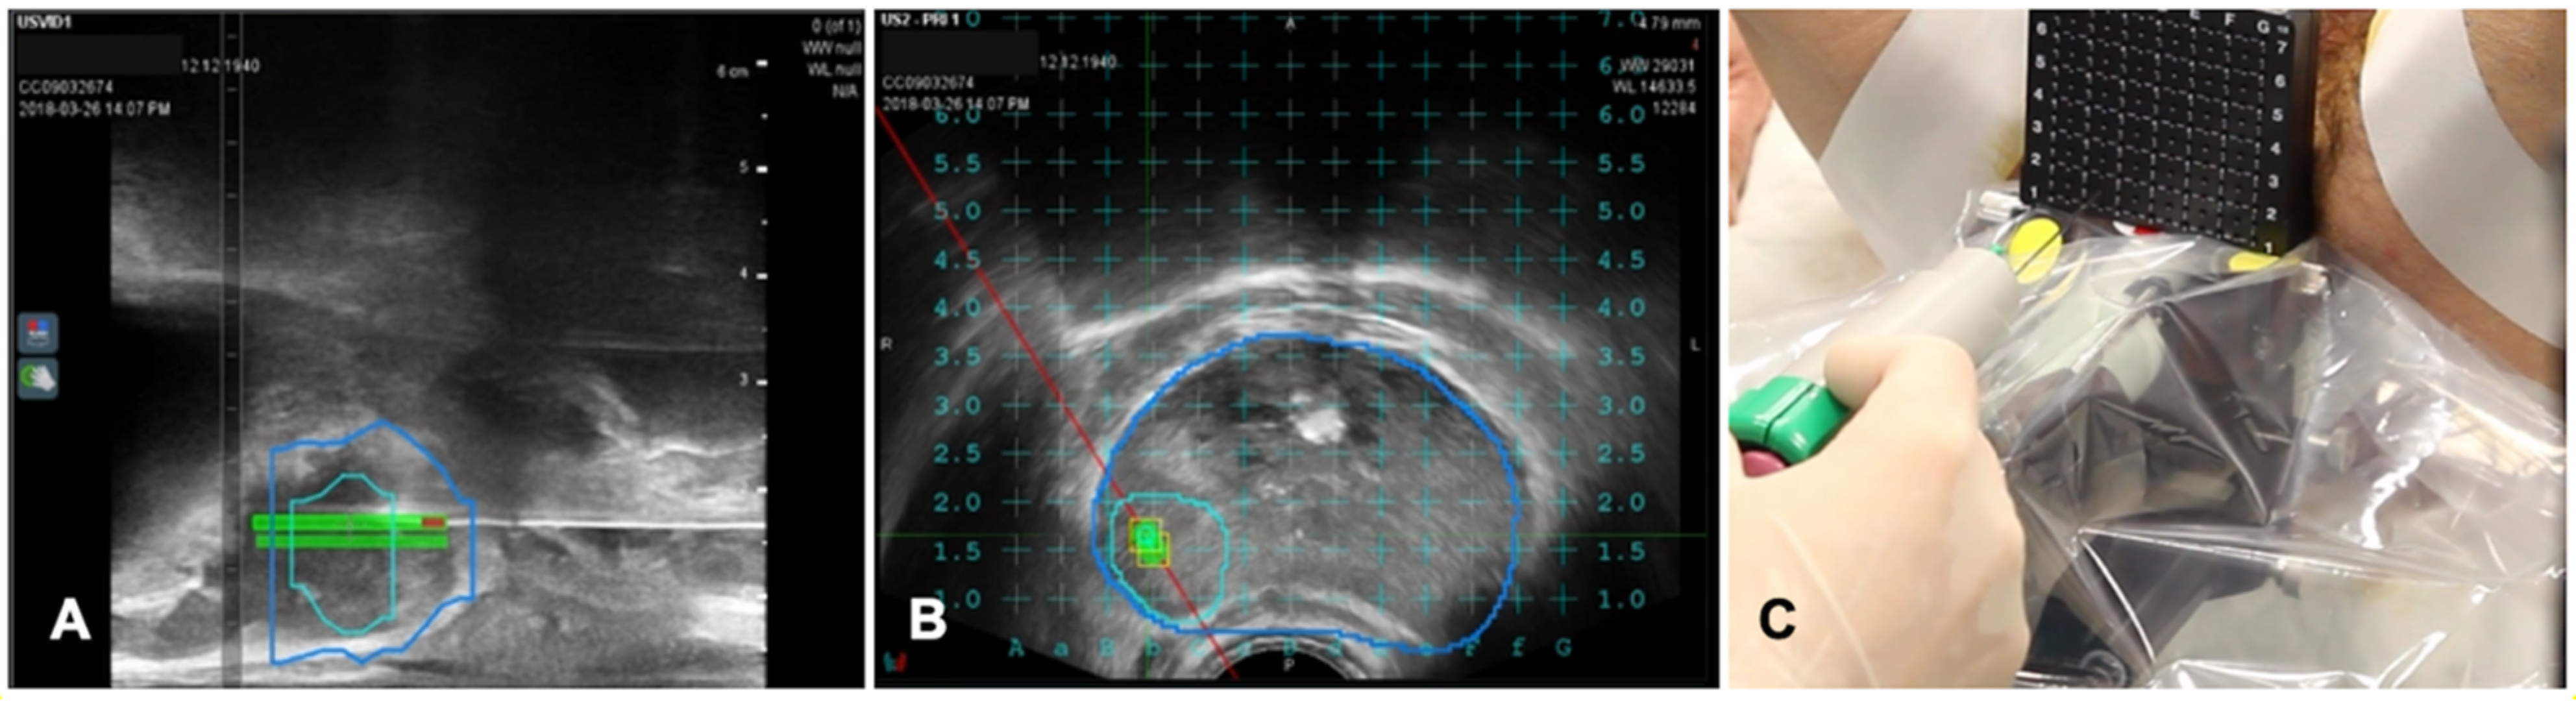

Figure 6. Case of biopsies of a magnetic resonance imaging (MRI) visible prostate nodule. (A) Parasagittal long axis view of intraprocedural ultrasound fused with regions of interest from MRI. Target lesion has been segmented in MRI images and is encompassed by the green line in the prostate volume (blue line). (B) Axial view of the target lesion (green line) in prostate parenchyma (blue line) derived from MRI. A reference grid is superimposed to select the appropriate space for needle placement. (C) A transperineal biopsy needle is then placed in the selected hole in the reference grid and advanced into the target lesion.

Transrectal US-guided biopsy technique (TRUSbx) was introduced nearly 30 years ago and it has been the standard-of-care to either confirm the diagnosis or exclude the presence of disease [48]. The major disadvantages of the TRUSbx are the systematic sampling errors [49]. These limitations have highlighted the need to improve the diagnostic information gained by the invasive prostate biopsies and maximize the detection of significant prostate cancers (sPCa), while minimizing the over-detection of insignificant diseases [50]. To overcome this issue, growing evidence support the use of multiparametric MRI (mpMRI) to perform targeted biopsies (TBx) [51]. In fact, the gold standard of MRI-guided TBx is the in-bore TBx in the MRI suite which can accurately sample lesions of interest with direct image confirmation of needle deployment within the target [52]. This technique is associated with not negligible costs, limited availability and does not allow for concurrent systematic sampling [52]. The application of FI, combining mpMRI data with TRUS (MRI/TRUS fusion) joins mpMRI images and the more comfortable US guidance. It demonstrated to be time and cost-saving, while preserving an adequate targeting accuracy [53,54]. An additional key advantage of MRI/TRUS fusion is that TBx can be combined with systematic biopsies, as recommended by the European Association of Urology (EAU) guidelines [55]. Several commercial software platforms have been developed to increase targeting accuracy that differ in both, technology (image acquisition and tracking mechanism) and biopsy route (transrectal or transperineal) [50]. TA is not routinely applied at prostate tissue, but experiences are increasing in this field, which represents a very promising field of application of TA for the future [56,57]. A case of biopsies of a prostatic nodule visible on MRI is shown in Figure 6.